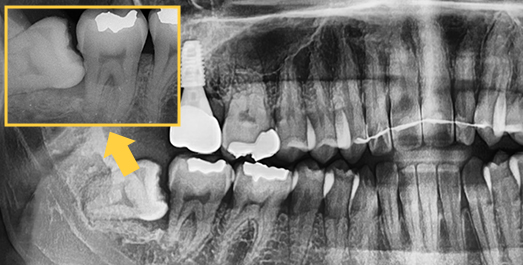

Some wisdom teeth erupt normally, but others may erupt at an angle, horizontally, or remain fully impacted. Wisdom teeth that do not erupt properly can disturb the dental arch and are difficult to clean, which may lead to decay of adjacent molars. In such cases, extraction is recommended.

Complex wisdom tooth cases, Seoul The Nature Dental Clinic

does not give up.

Extraction technique with nerve considerations

Using 3D CT, we evaluate the shape of the wisdom tooth, its roots, and surrounding nerves to support a safer extraction process.